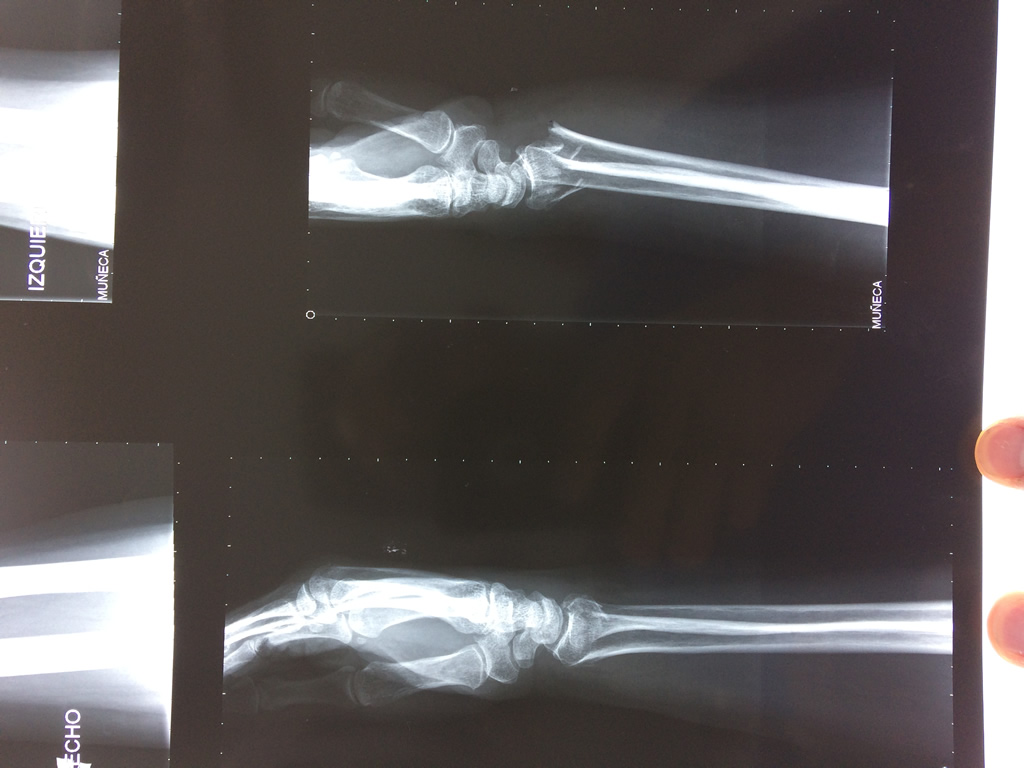

Los procedimientos más comunes en cirugía de la mano son aquellos destinados a reparar traumatismos, incluyendo lesiones de tendones, nervios, vasos sanguíneos, y articulaciones; huesos fracturados; y quemaduras, cortes, y otros daños de la piel.